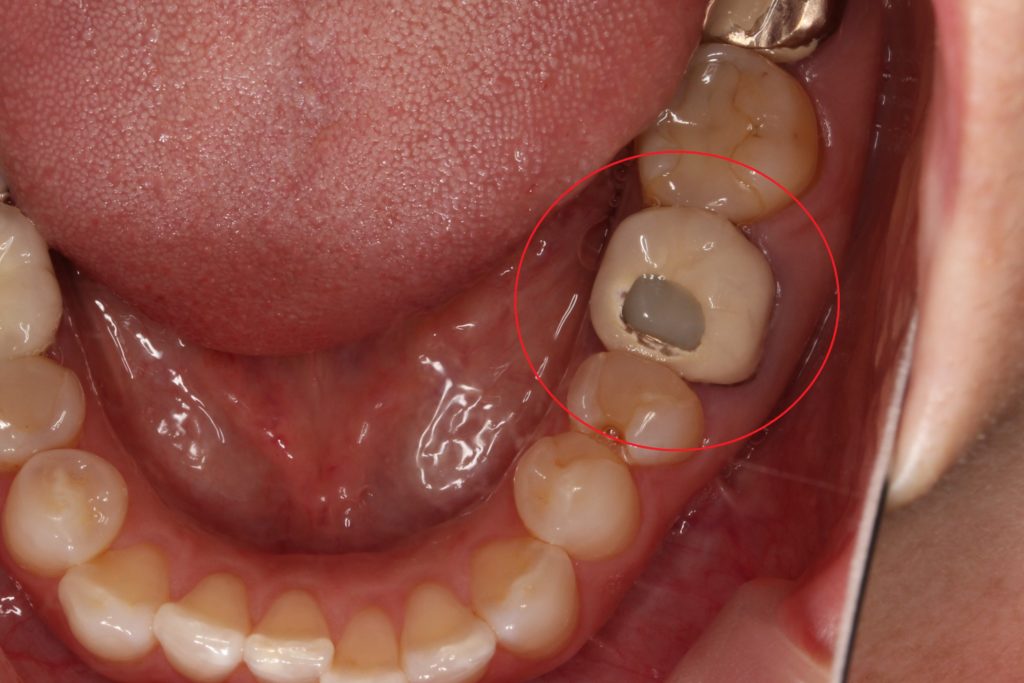

根の先が膿んだ被せ物

初診時のお口の写真です。

赤い丸の歯が、根の先が膿んで、レントゲン写真で黒くなっていました。

かぶせ物の歯なのですが、見た目が変な感じですね。

前の先生が、かぶせ物をしたまま、中を削って、削った穴にレジン(プラスティック樹脂)で埋めてあるためです。

何度も根管治療を行うも、治らず、

外側の歯ぐきを切って、外科的に膿んでいる所を治療したが経過は悪く、当院に来院されました。